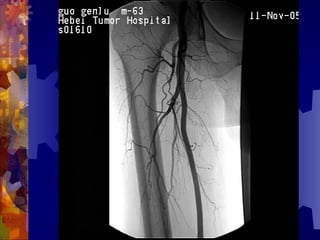

糖尿病足的检查

4. 足部 X- 线检查

5. 动脉造影(下肢)

男, 86 岁

双下肢多普勒血流图未探及血管

动脉造影血管闭塞